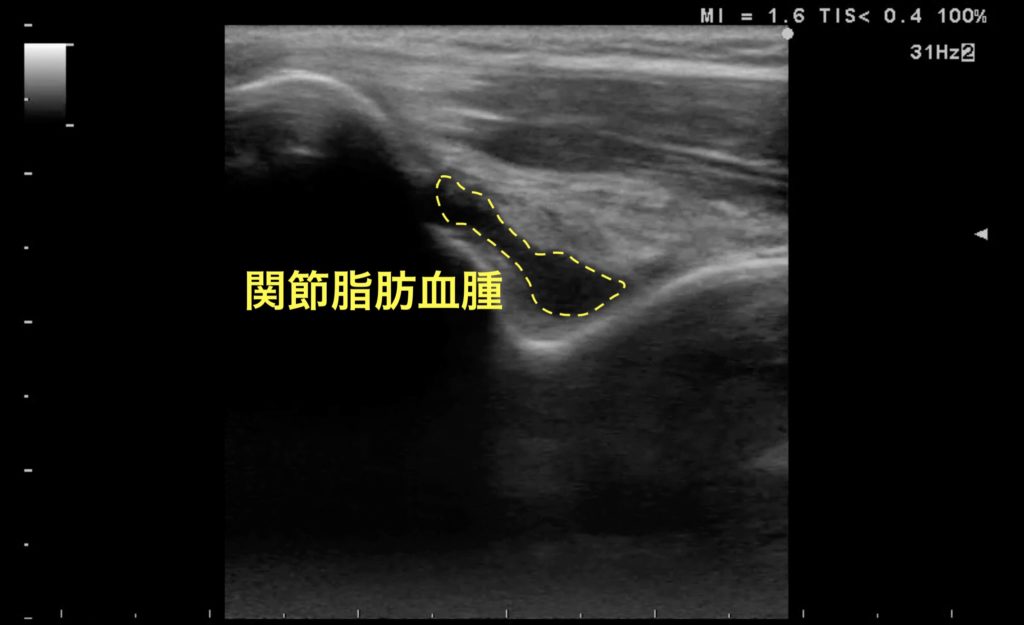

転倒時に右手を伸ばして突いた。みられる異常はなにか?

肘関節内血腫

肘関節内の骨折は、レントゲンではFat pad signとして検出される。超音波でも、肘関節を90度屈曲させ、上腕骨背側からリニアプローブを当てて肘頭窩の後方脂肪体(Fat pad)を観察することができる。同部位の血腫はレントゲンにおける後方Fad pad signと同等の意味を持つ。上の画像では肘頭窩内部に低エコー領域がみられ、関節内血腫(Lipohemarthrosis:関節脂肪血腫)が示唆される。これは関節内骨折に随伴する所見を意味し、特に小児では緊急性の高い上腕骨顆上骨折を疑う上でも重要な所見である。